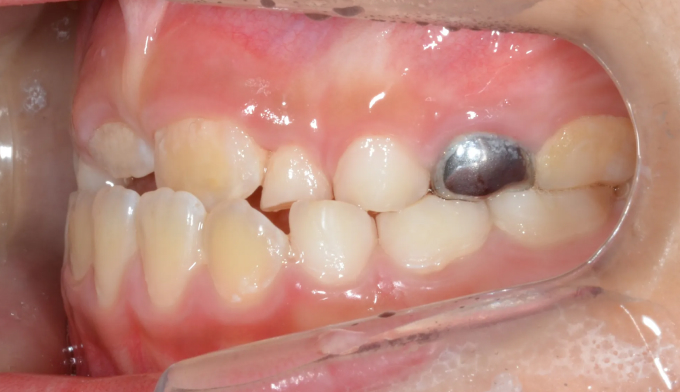

안모상으로 주걱턱 경향은 심해보이지 않고, 앞니의 약간의 반대교합만 관찰됩니다.

하지만 옆모습 엑스레이 분석시 주걱턱 수치가 높게 나와 성장교정이 필요한 케이스 입니다.

아래턱의 성장방향을 하방으로 바꿔주면서 상악의 전방견인을 시행하였습니다.

반대교합 교정은 심미적인 이유 뿐만이 아니라 기능적으로도 성장기의 아이들이 보다 더 편한 교합을 만드는데 유리합니다.